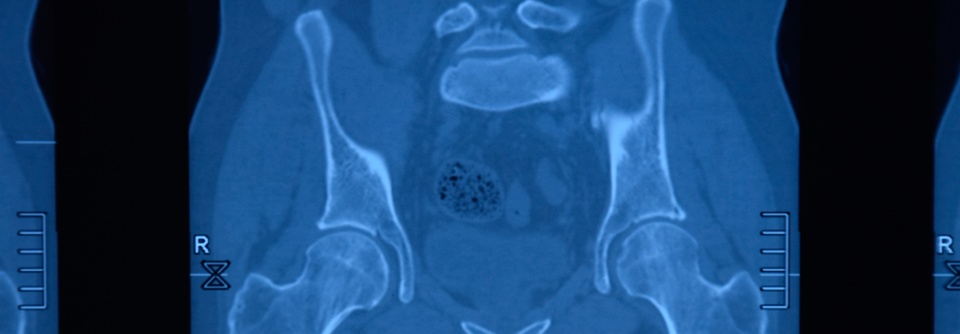

Übergeordnetes Therapieziel bei axSpA ist es, die radiografische Progression zu bremsen. Das scheinen auch NSAR zu können, wie 10-Jahres-Daten aus der GESPIC-Kohorte (German Spondyloarthritis Inception Cohort) deutlich machen. Murat Torgutalp, Charité – Universitätsmedizin Berlin, stellte eine aktuelle Auswertung von 243 Patienten mit axSpA vor, für die radiografische Daten zu zwei konsekutiven Zeitpunkten vorlagen.

Tatsächlich bremsten die NSAR die mittels Modified Stoke Ankylosing Spondylitis Spinal Score (mSASSS) gemessene radiografische Progression über zwei Jahre hinweg signifikant. Vor allem traf dies in der Subgruppe von Patienten mit bereits radiografisch dokumentierter axSpA zu. COX-2-selektive Substanzen erwiesen sich insgesamt als etwas effektiver im Vergleich zu unselektiven NSAR.

Kann man die radiografische Progression durch konsequente Ergänzung einer Anti-TNF-a-Therapie mit NSAR noch besser bremsen als mit TNF-a-Blockern allein? Dieser Frage ging die offene, randomisierte CONSUL-Studie nach, die Prof. Dr. Fabian Proft, Charité – Universitätsmedizin Berlin, vorstellte. Als NSAR wurde der selektive COX-2-Hemmer Celecoxib und als TNF-a-Blocker Golimumab eingesetzt. Die eingeschlossenen Patienten wiesen eine aktive radiografisch nachgewiesene axSpA mit hoher Wahrscheinlichkeit für eine Progression auf.